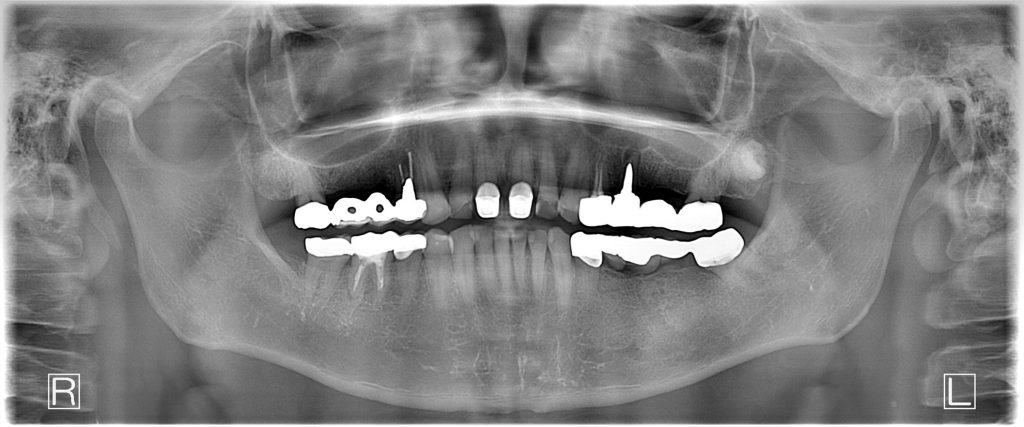

50代、男性、左上に違和感があることを主訴に来院され、インプラント治療を行いました。

| 診断結果 | 左上5番歯根破折 |

| 治療内容 | 抜歯即時インプラント |

| 治療期間 | 10週間 |

| 治療費用 | ¥946,000(税込) |